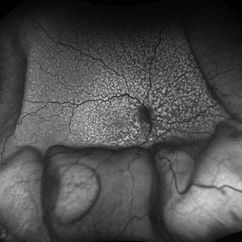

Multimodal Imaging in CHRPE

Multimodal Imaging in CHRPE

Mar 6 2025 by Gerardo - Montante Montelongo, MD

Fundus photograph of an 83-year-old male with a history of Diabetes, smoking, cataract surgery on the right eye in 2022, and open-angle glaucoma. Asymptomatic. Indirect ophthalmoscopy revealed 80% excavation, peripapillary atrophy, and a hyperpigmented perifoveal lesion with 35% atrophy, 10% drusen, and 5.1 mm diameter, corresponding to a CHRPE. At multimodal imaging, FFA shows hypoautofluorescence of the lesion, OCT shows preservation of internal retinal layers, atrophy of external retinal layer, with an RPE disruption, and posterior shadowing. USG shows a flat hyperechoic lesion 5.1 mm in diameter and 1.32 mm in thickness, solid and with high internal reflectance.

Photographer: Gerardo Montante-Montelongo, MD, Mexican Institute of Ophthalmology

Imaging device: Clarus 700

Condition/keywords: congenital hypertrophy of the retinal pigment epithelium (CHRPE), multimodal imaging